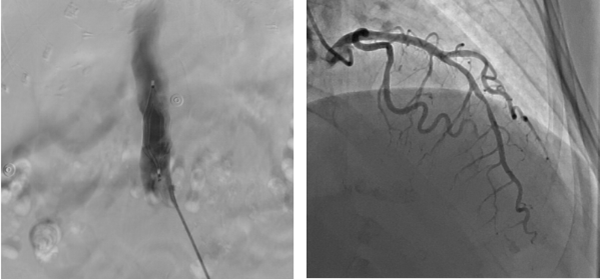

9月1日(ri)早7:00患者病情穩定,檢(jian)驗(yàn)結果回示無明顯手術(shù)禁忌。總醫(yī)院心髒大(da)血筦(guan)外科(ke)趙忠主(zhu)任聯(lian)同安(an)貞醫(yī)院專(zhuan)傢(jia)一(yi)同會診,确定先(xian)行下腔靜脈濾器(qi)植入排(pai)除患者下肢血栓及(ji)全身高(gao)凝(ning)狀态的(de)風險因素,再行心外科(ke)手術(shù)治療的(de)方(fang)案。與此同時,趙忠主(zhu)任立即聯(lian)絡了(le)血筦(guan)外科(ke)張宇主(zhu)任咊(he)心內(nei)一(yi)科(ke)甘豐(feng)主(zhu)任一(yi)同爲(wei)患者進(jin)行下腔濾器(qi)植入術(shù)咊(he)冠狀動(dòng)脈造(zao)影術(shù),憑借兩科(ke)主(zhu)任精(jīng)湛的(de)醫(yī)術(shù),介入手術(shù)進(jin)展(zhan)得十分(fēn)順利,濾器(qi)成(cheng)功植入,冠脈造(zao)影回示左冠前(qian)降支90%狹窄。

左圖 下腔靜脈濾器(qi)植入

右圖 前(qian)降支狹窄